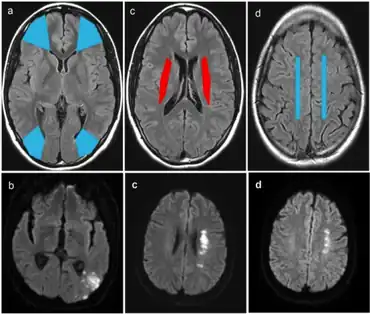

- Cortical watershed strokes (CWS), or outer brain infarcts, are located between the cortical territories of the anterior cerebral artery (ACA), middle cerebral artery (MCA), and posterior cerebral artery (PCA).[3]

- Internal watershed strokes (IWS), or subcortical brain infarcts, are located in the white matter along and slightly above the lateral ventricle, between the deep and the superficial arterial systems of the MCA, or between the superficial systems of the MCA and ACA.[3]

Diagnosis

Diagnosis of a cerebral vascular accident begins with a general neurological examination, used to identify specific areas of resulting injury. A CT scan of the brain is then used to identify any cerebral hemorrhaging. An MRI with special sequences called diffusion-weighted MR imaging (DWI), is very sensitive for locating areas of an ischemic based stroke, such as a watershed stroke.

Strokes after cardiac surgery

Although the mechanism is not entirely understood, the likelihood of a watershed stroke increases after cardiac surgery. An experiment conducted in a five-year span studied the diagnosis, etiology, and outcome of these postoperative strokes. It was observed that intraoperative decrease in blood pressure may lead to these strokes and patients who have undergone aortic procedures are more likely to have bilateral watershed infarcts. Furthermore, bilateral watershed strokes are associated with poor short-term outcomes and are most reliably observed by diffusion-weighted imaging MRI. Thus future clinical research and practice should focus on the identification of bilateral stroke characteristics. This identification can help discover affected areas and increase correct diagnosis.[21]